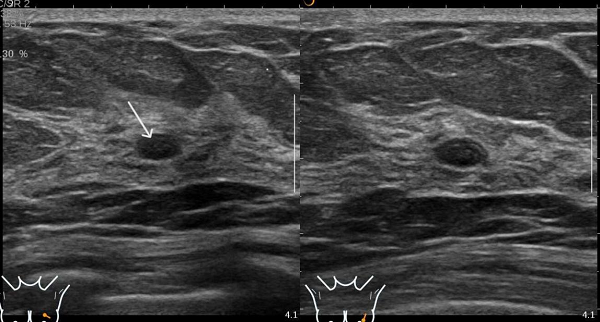

患者B钼靶检出多发钙化灶,超声虽未显示钙化,但发现了钼靶未显示的实性结节(如图3、4)。

图3 患者B的钼靶图像,显示乳腺多发钙化灶(图中画圈处)

图4 患者B的超声图像,显示未见钼靶所示钙化灶,但扫查到乳腺实性低回声结节(图中箭头处)